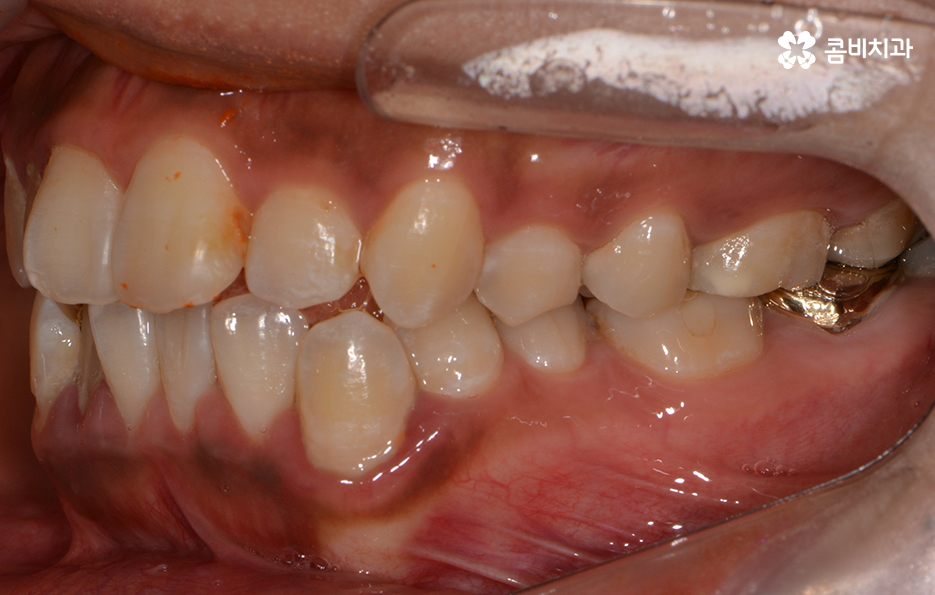

(좌) 얼굴을 고려하여 돌출입을 개선하는 치료 계획을 세움, (우) 사랑니 발치와 상악 14,24 / 하악 34,44 치아 발치 진행

발치는 꼭 해야 하나요?

교정을 하시는 모든 분들이 발치를 하는 것은 아니지만

만약 본인이 발치를 해야 하는 대상이라고 생각한다면

당연히 두려운 마음부터 들지 않을까 합니다.

하지만 치아교정은 결과가 중요한 만큼 교합부터

심미적인 안모, 가지런한 치열 등에 대해서

모든 부분이 조화로워야 한다는 점에서 치아의 이동

공간이 확보 되어야 하고 얼굴의 변화 등을 위해

필요한 경우에는 발치를 해야 합니다.